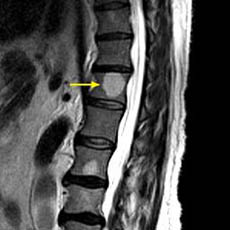

Lumbar Spine |

|

Recumbent, Weightless |

Upright, Weight-Bearing |

Figure 8.

Figure 8a-8d.

Further examples of the exceptional anatomic detail

made visible by the DISCOVERY

of Damadian of the pronounced differences in the decay

rates (relaxations) of the NMR signals

of the body's normal tissues (Figure

6). The DISCOVERED

differences supply the pixel amplitude differences

"PIXEL CONTRAST (IMAGE DETAIL)"

that produce, for the first time in medical history,

the detailed visualization of normal human anatomy

MRI is noted for. Note the visualization of the